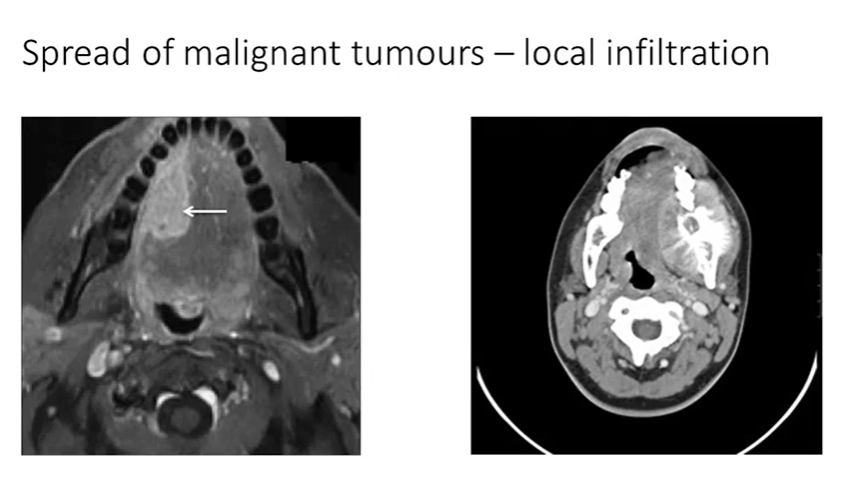

Spread of malignant tumours 5

infiltrate local tissues

spread of malignant squamous carcinoma local infiltration

undergo genetic changes - lose those tight attachments

Lose tight attachments

Disrupt / dissolve the basement membrane - no longer confined

Enter connective tissues / acquire mobility and gain destructive powers to damage the stromal tissues that are in their way

notice the infiltrating islands of cells that extend from the surface epithelium on the top right

they’re entering and breaking up the muscle layers - which still remain quite bright pink

lots of associated inflammation

the tumour islands do bear some resemblance to the surface squamous epithelium - but more chaotic version of it

normal epithelium, beneath it, there’s a very similar looking island (tumour) - keratin pink centre - looks chaotic, atypical cells

invasive infiltrating squamous cell carcinoma